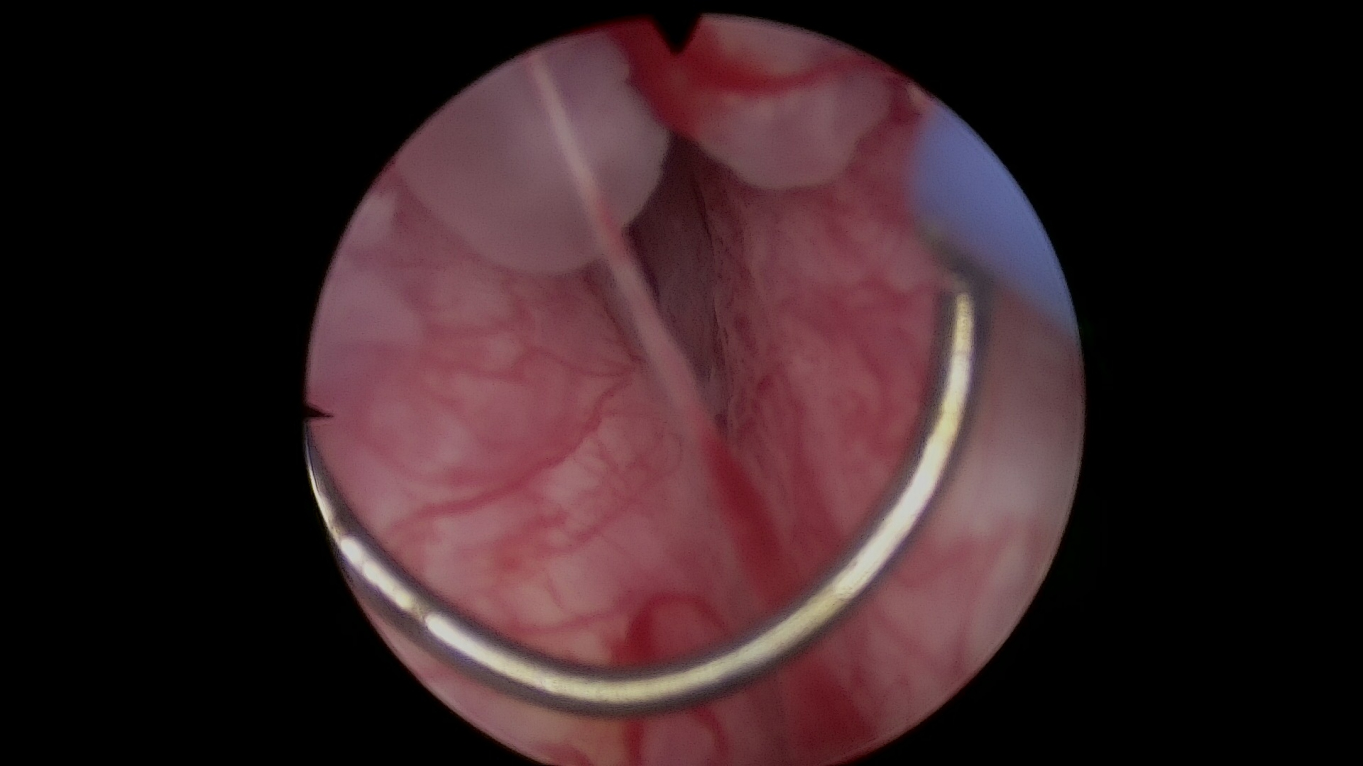

1.超高清成像系统、输尿管镜、膀胱镜等

泌尿系统结石的钬激光碎石